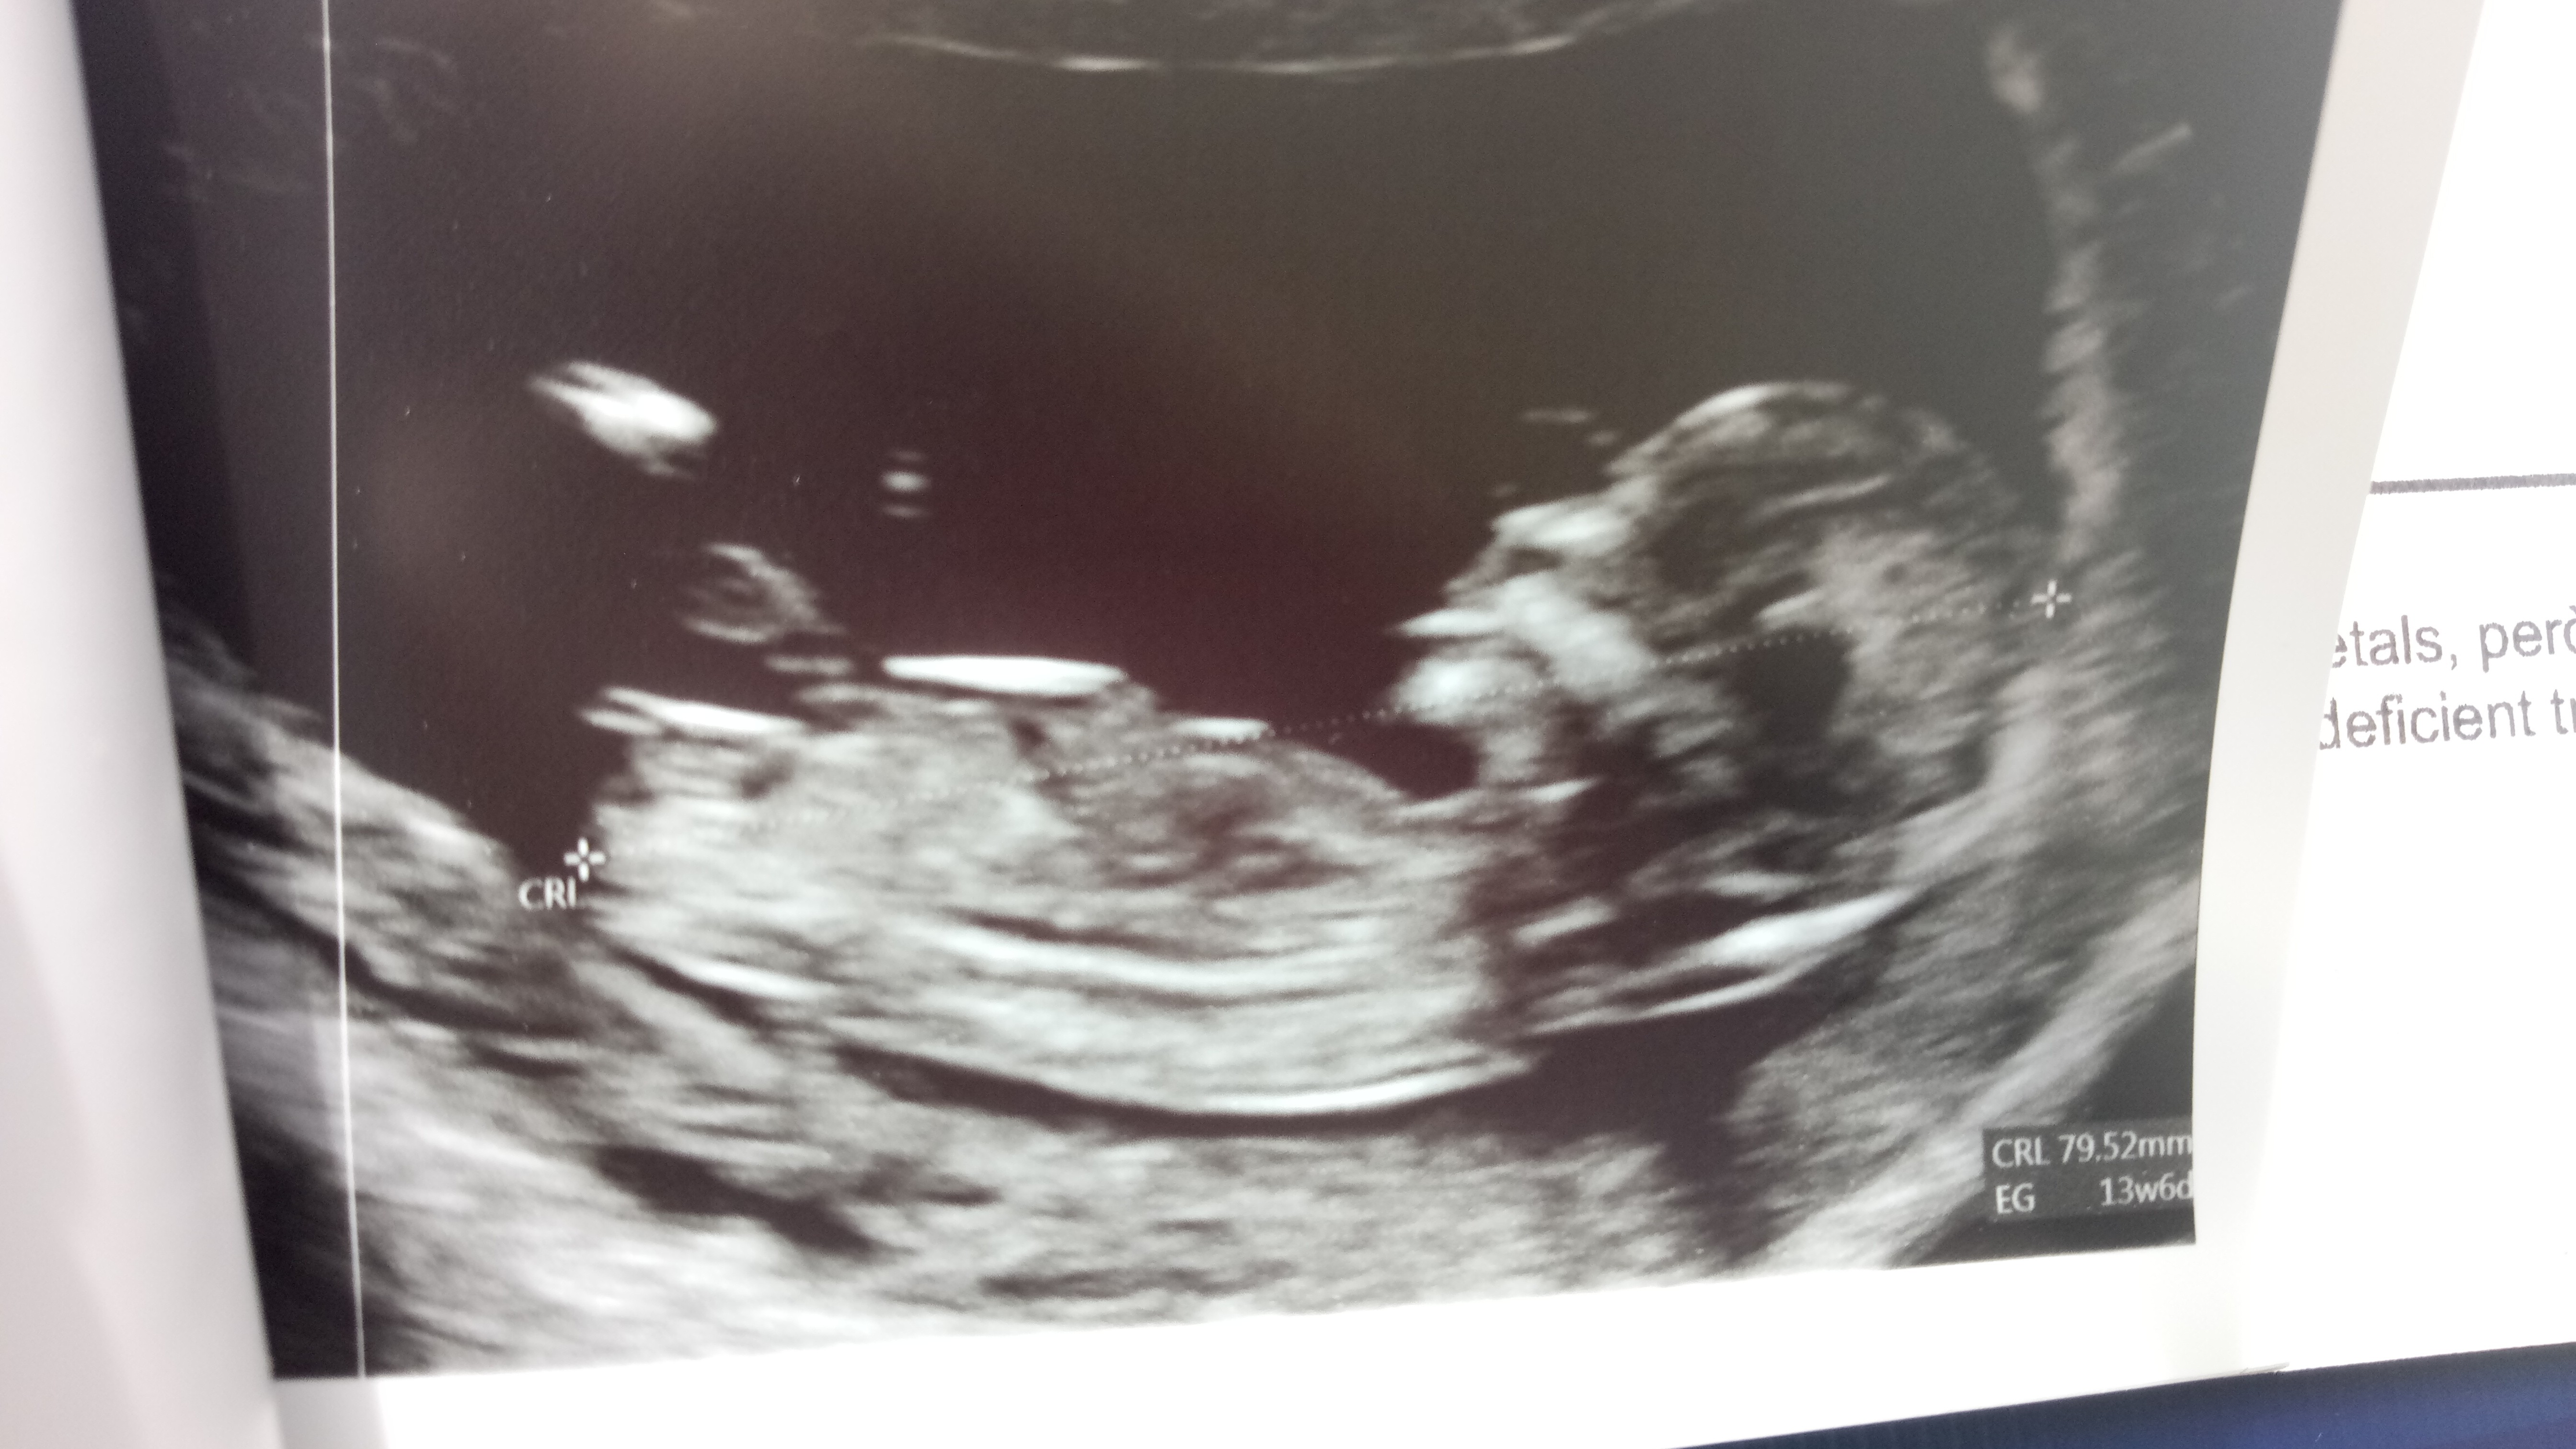

Oto mój Mały-Wileki człowiek!!!

CRL 64,4 mm

NT 2,2 mm

Wszystko w normie :) i na miejscu.

Rączki, nóżki, brzuszek, żołądek, pęcherz, podział mózgu jak należy!

Według OM jestem 13t według USG 12t6d.